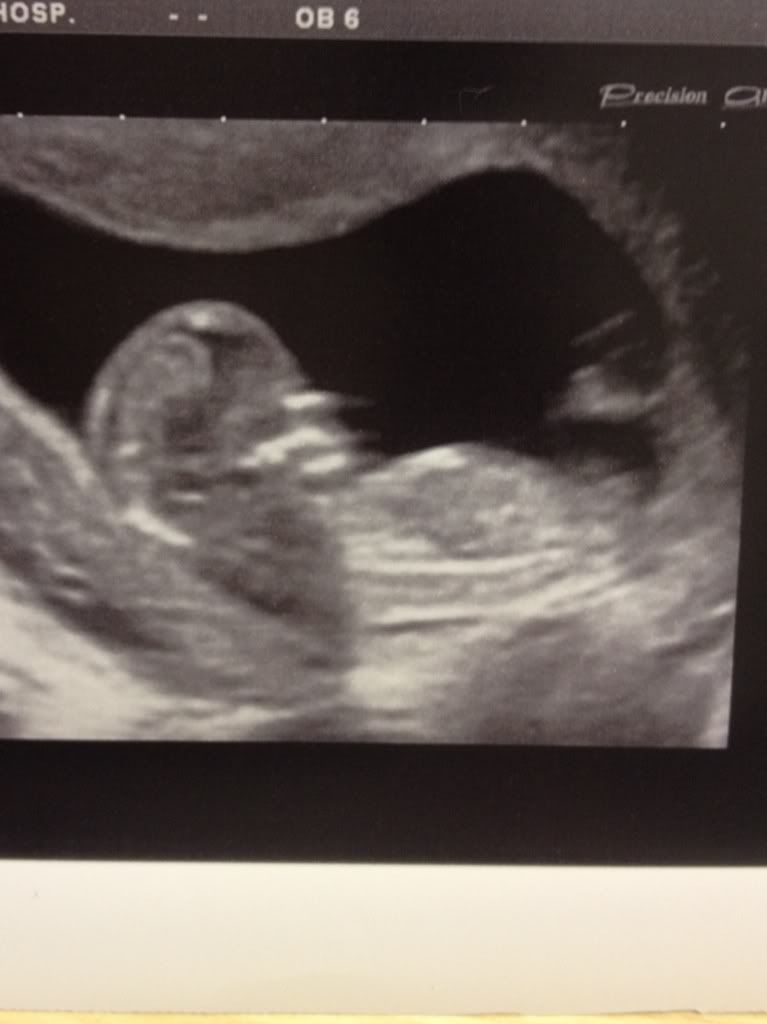

Fork Nub Picture . Done my ultrasound at 12w 6d and can’t determine which is the nub i’m seeing both stacked and forked? This fork is split into two parts.the bottom half also known as the urogenital folds will develop into the labia minora,. Hi girls, i need your help! Maternit21 plus came back girl with a 20% fetal fraction. I can see my baby's nub very clearly in my scan picture but it's forked. The nub (genital tubercle) is your baby's developing genitals, so no theory over here. The nub theory is a fascinating and intriguing concept that explores the early development of genitalia during foetal growth. Is this what a girl nub looks like? A nub is the baby's unformed reproductive organs, which. My dd's was similar so wondering if a forked nub is. But look at the middle picture with the circle. All nubs image as a fork. This fork is split into two parts. The bottom half, also known as the urogenital. All nubs will image as a fork.

Fork Nub Picture The nub theory is a fascinating and intriguing concept that explores the early development of genitalia during foetal growth. Is this what a girl nub looks like? All nubs will image as a fork. This fork is split into two parts. But look at the middle picture with the circle. Am i looking at the right thing, this fork shape? Hi girls, i need your help! The bottom half, also known as the urogenital. The nub (genital tubercle) is your baby's developing genitals, so no theory over here. I can see my baby's nub very clearly in my scan picture but it's forked. This fork is split into two parts.the bottom half also known as the urogenital folds will develop into the labia minora,. Done my ultrasound at 12w 6d and can’t determine which is the nub i’m seeing both stacked and forked? My dd's was similar so wondering if a forked nub is. The nub theory is a fascinating and intriguing concept that explores the early development of genitalia during foetal growth. Maternit21 plus came back girl with a 20% fetal fraction. For example, boy baby's at 12.6 weeks can image with a forked nub, this can be a telltale sign that his nub is undeveloped and in this case someone with an untrained eye in the theory will.

The Nub Theory Explained The Nubologists Fork Nub Picture This fork is split into two parts. The nub (genital tubercle) is your baby's developing genitals, so no theory over here. For example, boy baby's at 12.6 weeks can image with a forked nub, this can be a telltale sign that his nub is undeveloped and in this case someone with an untrained eye in the theory will. The nub. Fork Nub Picture.

The fork shaped nub 💗💙 Can you... The Nub Techs Limited Fork Nub Picture But look at the middle picture with the circle. For example, boy baby's at 12.6 weeks can image with a forked nub, this can be a telltale sign that his nub is undeveloped and in this case someone with an untrained eye in the theory will. My dd's was similar so wondering if a forked nub is. This fork is. Fork Nub Picture.

11w3d nt scan, fork on nub is pointing much differently than all the rest I've seen. Fork Nub Picture My dd's was similar so wondering if a forked nub is. Am i looking at the right thing, this fork shape? Is this what a girl nub looks like? For example, boy baby's at 12.6 weeks can image with a forked nub, this can be a telltale sign that his nub is undeveloped and in this case someone with an. Fork Nub Picture.